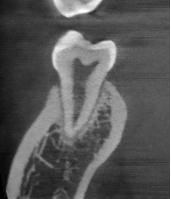

a. Observar radiográficamente las características anatómicas y dimensionales de los caninos superiores e inferiores respecto a dientes adyacentes (Figura 11).

b. Identificar radiográficamente la posición en que se encuentra el canino, respecto a los dientes adyacentes (Figura 12).

c. Determinar que angulación y posición existe entre el eje longitudinal

del canino respecto al plano oclusal, donde “V” es vertical, “M” es mesioangular, “H” es mesiohorizontal, “MI” vertical invertido, “D” distohorizontal (Figura 13).